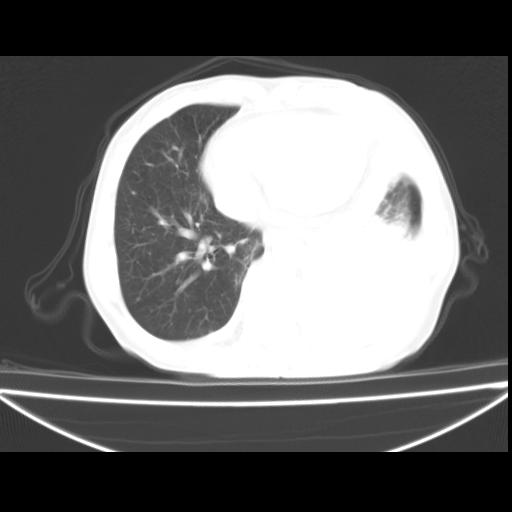

以下是引用随光逐影在2010-3-24 19:15:00的发言:[br]结合病史,考虑双肺及纵隔淋巴结多发转移、左侧胸膜转移并左侧大量胸水,左下肺膨胀不全。

以下是引用zxl51642在2010-3-24 18:49:00的发言:[br]结合乳腺癌术后病史,考虑双肺及纵隔淋巴结多发转移、左侧胸膜转移并左侧大量胸水、左下肺膨胀不全。